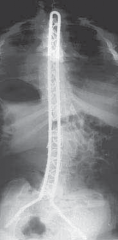

3. Final radiographs are taken to confirm coronal and sagittal alignment (

TECH FIG 4B–D

B.

AP radiograph of the patient in Figure 1 shows postoperative

correction of coronal plane deformity.

CDEFTECH FIG 4•

(continued)

Clinical photographs show correction of pelvic obliquity (

C

) and good sagittal plane alignment (

D

). Preoperative (

E

) and postoperative (

F

) lateral radiographs of patient with severe hyperlordosis corrected with unit instrumentation and pedicle screws used to correct lordosis in the apex of the deformity.